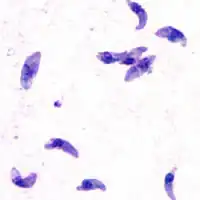

![]() Trofozoity T. gondii | |

Eucoccidiorida – rząd mikroskopijnych, wytwarzających zarodniki, jednokomórkowych pasożytów z gromady Conoidasida. Należy do podgromady Coccidia. Wśród pierwotniaków należących do tego rzędu są pasożyty, którymi mogą zarazić się ludzie oraz oswojone dzikie zwierzęta (np. ptaki). Do tych pasożytów zaliczają się Toxoplasma gondii, która powoduje toksoplazmozę oraz Cystoisospora belli, która powoduje izosporydozę.